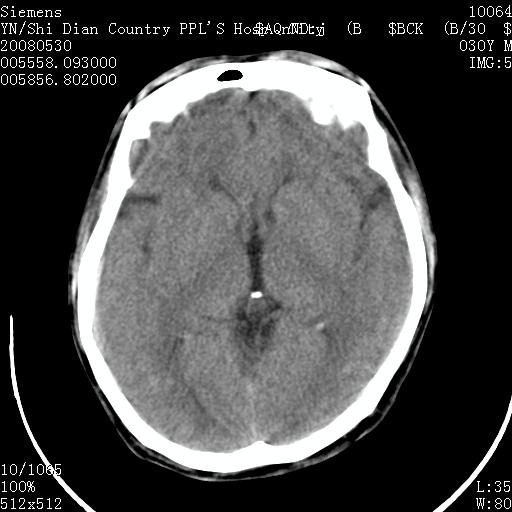

以下是引用随光逐影在2008-7-10 15:19:00的发言:[br]1)考虑左侧尾状核钙化。2)透间隔间腔与vergae腔并存。

以下是引用卜一在2008-7-10 16:43:00的发言:[br]1)考虑左侧尾状核钙化。2)透间隔间腔形成。支持!